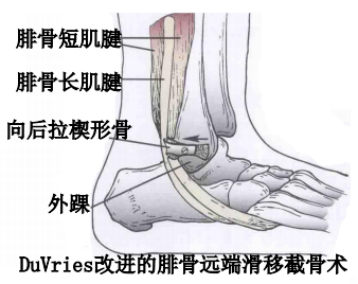

(3)手术方法可分为以下5类:

如不合并其他病理改变,可将支持带和骨膜直接缝合于外踝骨质上。

SPR撕脱开放手术锚钉修复

SPR撕脱关节镜手术锚钉修复

使用跟腱、跖肌腱、腓骨短肌腱等肌腱的一部分加强固定腓骨支持带。

通过切除腓骨后方部分骨质,可以加深腓骨沟,改变、并增加了腓骨肌腱的稳定。

内镜下腓骨沟加深手术

大部分急性损伤可以使用直接缝合修复,对慢性损伤则需根据患者的具体病理改变选择,如单纯的支持带结构损伤,可以直接缝合修复。如果直接修复不够稳定,需用其他组织加强。如果腓骨外踝窝较浅时,就需要使用加深手术。